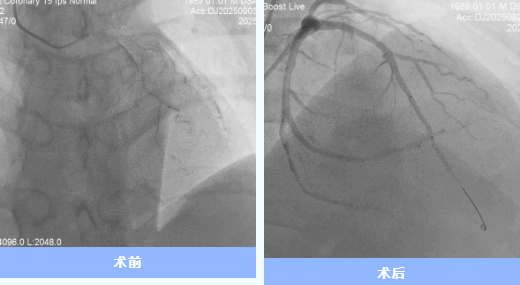

9月29日世界心臟日,35歲的代先生從隨州市中心醫(yī)院康復(fù)出院,將錦旗交予醫(yī)護(hù)人員手中。這背后,是一場(chǎng)由多學(xué)科協(xié)作的20余天的“生命保衛(wèi)戰(zhàn)”。 01雷霆救治:與死神競(jìng)速 9月3日17時(shí),代先生因“胸痛不適1天,加重1 ...